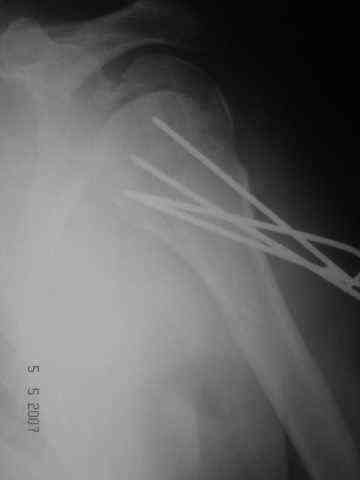

Dear all, A heavy built 30-year-old male patient sustained fracture dislocation of left shoulder about 8 months back.

For this ORIF with K-wires was done elsewhere. K-wires were removed at 6 weeks and patient advised physiotherapy. He has been doing physio dedicatedly since then.

Looking at his previous x-rays, I was thinking of refixing the greater tuberosity, however got an axillary view done today which was never done during this period and this shows non-union.

He can’t be left as such as he wants movement to tie his turban.

Kindly advise about further management.